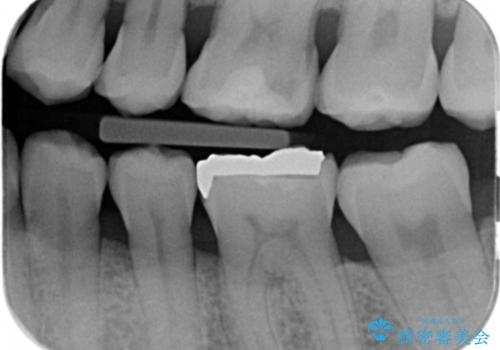

- 昔他院で虫歯治療をしたところが虫歯が再発したとのことで来院。

古い材料(プラスチックの樹脂)をとり、拡大鏡下で虫歯を全て取り除き、

ゴールドインレーにて治療しました。

歯の外側の面が少し欠けていて、そこの部分を覆う(ゴールドの範囲が広くなる)か

そこの欠けてる部分は虫歯ではないので削らないで、最小限にして詰め物を作るか相談したところ

欠けているところは何十年も昔から欠けていて特に何もない。なるべく歯を削りたくないとの事だったので

最小限で詰め物の治療をしました。